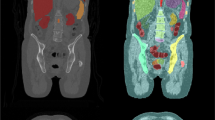

The pediatric computed tomography (CT) volume is acquired at a low dose because radiation is harmful to young children. Consequently, the pediatric CT volume has lower signal-to-noise ratio, which makes organ segmentation difficult. In this paper, we propose a liver segmentation algorithm for pediatric CT scan using a patient-specific level set distribution model (LSDM).

The patient-specific LSDM was constructed using a conditional LSDM (C-LSDM) conditioned on age. Furthermore, a patient-specific probabilistic atlas (PA) was generated using the model, which became a priori to the maximum a posteriori-based segmentation. The patient-specific PA generation by the C-LSDM using kernel density estimation was quicker than the conventional PA generation method using random numbers, and also, it was more accurate as it did not include any approximations.

The liver segmentation algorithm was tested on 42 CT volumes of children aged between 2 weeks and 7 years. In the proposed method, the calculation time of the PA was about 9 s for the single Gaussian method, while it was 337 s for the conventional PA generation method using random numbers. Furthermore, using the kernel density estimation, median and 25%/75% tile of the generalized Dice similarity index between the PA and the correct liver region were found to be 0.3443 and 0.3191/0.3595. The Dice similarity index in the segmentation was 0.8821 and 0.8545/0.9085, which are higher than those obtained by the conventional method, and requires lower computational cost.

We proposed a method to quickly and accurately generate a PA, combined with C-LSDM using kernel density estimation, which enabled efficient calculation and improved segmentation accuracy.